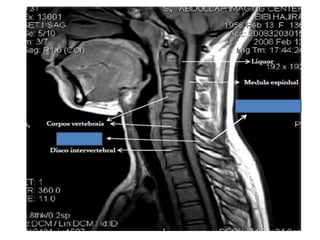

• A coluna vertebral é dividida em cinco

regiões: Cervical, Torácica, Lombar,

Sacro e Coccix.

• São 7 vértebras cervicais, 12 torácicas, 5

lombares, 5 sacrais e cerca de 4

coccígeas.

COLUNA CERVICAL

C1 – Atlas

C2 – Axis

C3 a C7: Corpo, arco neural posterior,

lâmina, pedículos, processos transversos

e espinhosos.